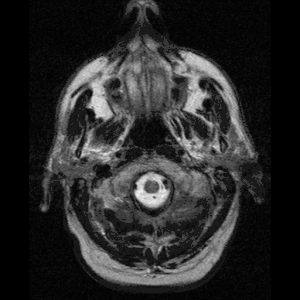

Neuroferritinopathy is most commonly diagnosed using MRI and other neuroimaging techniques.[1] MRIs help identify the iron deposits in the cerebellum, basal ganglia, and motor cortex common to neuroferritinopathy.[8] MRIs of affected individuals also show mild cerebellar and cerebral atrophy, or tissue breakdown, and gas cavity formation in the putamen.[8] Most importantly, the MRIs show misfolded ferritin proteins and iron deposits in the glial cells of the caudate, putamen, globus pallidus, cerebral cortex, thalamus, and purkinje cells, causing neuronal death in these areas.[8]

-

a)High signal caudate and lenticular nuclei b) long echo time in deep left cerebellum -

MRI